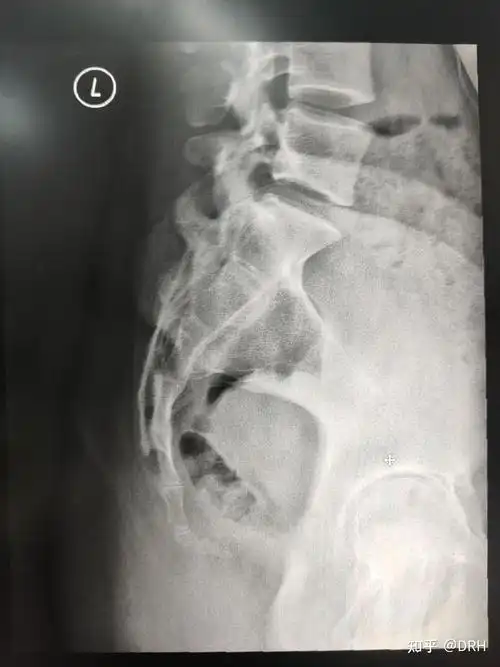

尾椎l5向后滑脱1/4 1度